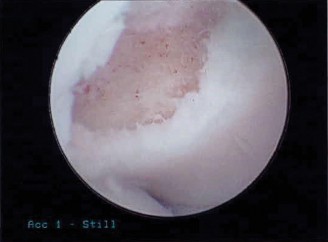

The patient undergoes conservative management consisting of rest, anti-inflammatory medications, and physical therapy. After six months, he is still not able to return to play and has progressively worsening symptoms with attempted throwing. He has a moderate elbow effusion as well as a 20-degree flexion contracture. An elbow MRI arthrogram is obtained and shown (Fig. 2–112). He elects to proceed with elbow arthroscopy. Intraoperative arthroscopic images are shown (Figs. 2–113 and 2–114).

Figure 2–113